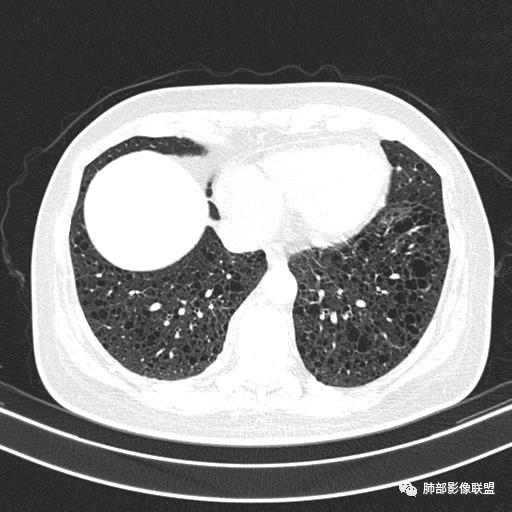

双肺弥漫囊腔,累及肋膈角,囊腔形态相对规则单一。

CT平扫示双肺弥漫分布大小不等囊状薄壁透光区,无内、中、外带分布差异,间质稍示增厚。拟LAM

女,46,活动性气喘1年。苯吸入史半年。胸部CT:两肺弥漫囊腔,上至肺尖,下至肋膈角,形态类似小囊腔。考虑:LAM,鉴别LIP,BHD,PLCH等。

CT表现:双肺弥漫大小不等的薄壁囊腔,囊壁<2mm,外形规则,血管影多位于囊腔周围,囊腔之间肺组织正常,随着疾病进展到晚期,囊腔变大、增多,不可胜数,囊腔可融合成较大的囊,与肺气肿相似,形成间质性肺纤维化。部分病例可出现结节影。